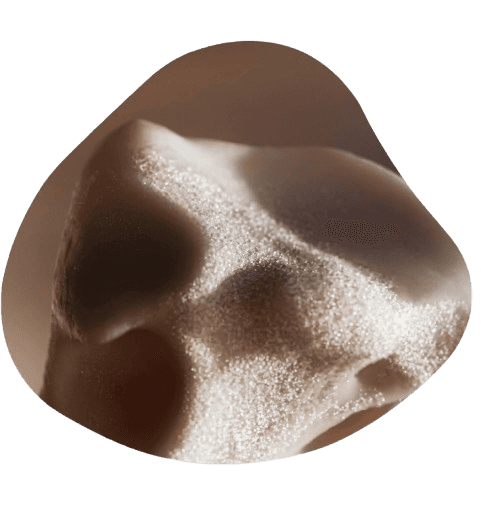

Completely Radiation Free

REMS uses ultrasound, not X-ray, making it entirely safe for regular reassessment over time.

More Than Just Density

REMS assesses both bone mineral density and bone quality, giving a more complete and clinically meaningful picture of your skeletal health.

DXA Accuracy, Without the Radiation

Revolutionary REMS technology delivers gold-standard accuracy with the safety and comfort you deserve.